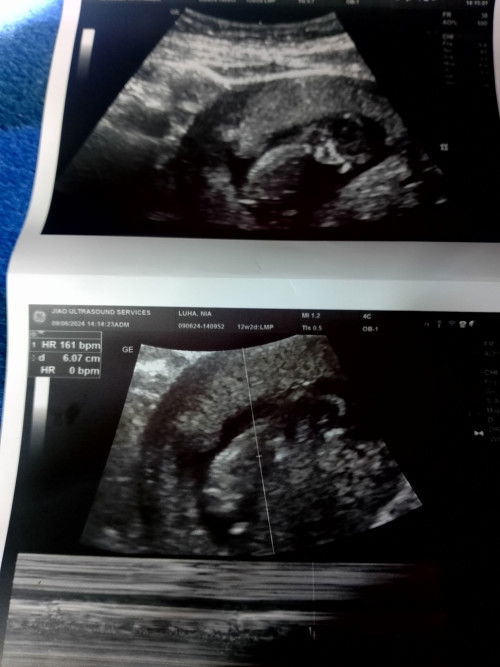

#12 weeks preggy here😍 thankful kasi healthy at malikot si baby sa tummy ko😍😍 i loveyou bebe😍😍